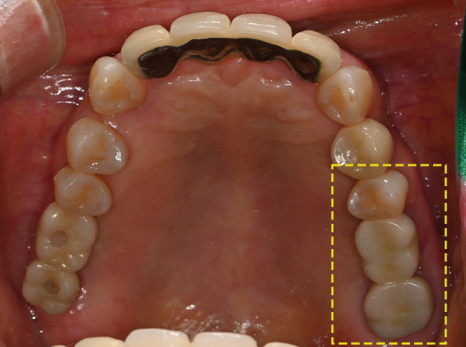

🔷 가장 좋은 임플란트를 선택한 환자분 이야기

2025.05.25

이 환자분은 고작 19세입니다.

어린 나이에 충치로 인해 어금니를 잃고,

임플란트 치료를 결심하게 되었는데요.

하지만 이 환자분에게는

특별한 고민이 필요했습니다.

“아직 너무 어리다.

앞으로 이 임플란트를 수십 년 써야 한다.”

2025.05.31

그래서 저희는 세계에서 가장 오래 쓰이는,

그리고 가장 튼튼하다고 인정받는

스위스 스트라우만 임플란트를 추천드렸고

수술을 진행하였습니다!

구강 내 상황을 면밀하게 고려하여

올바른 위치 및 방향대로

임플란트를 잘 식립해주었답니다!